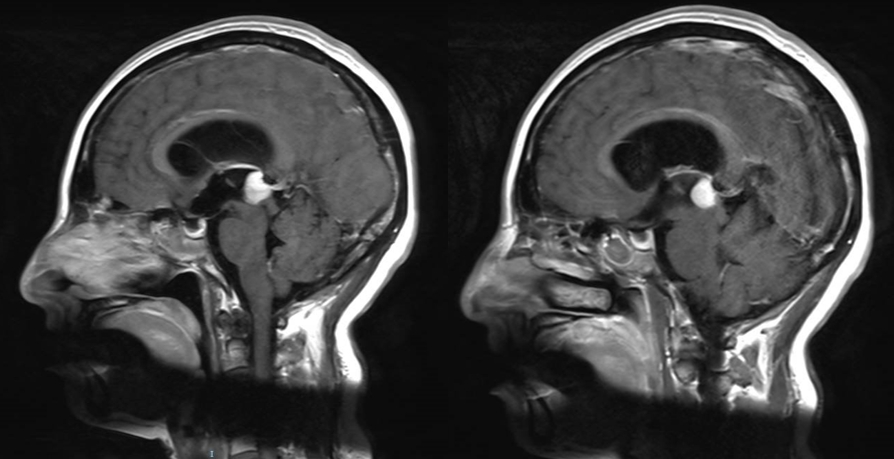

诊治过程:结合患者临床表现及影像学表现,初步诊断考虑为三脑室后部胶质瘤合并梗阻性脑积水可能性大,术前制定的手术方案为经胼胝体穹隆间入路三脑室后部肿瘤切除术+脑室镜辅助下三脑室底造瘘术,该手术方式既可切除肿瘤获取病理,同时可行三脑室底造瘘解决脑积水症状。术中采用冠状缝前额部弧形切口,术中沿纵裂牵开双侧大脑半球,探及胼胝体,沿中线切开胼胝体,分离双侧透明隔,暴露双侧穹隆,严格沿中线分离双侧穹隆,保护两侧穹隆的完整,避免引起术后的记忆力障碍,牵拉开双侧穹隆,进入中间帆,显露并分离双侧大脑内静脉继续向下,经脉络膜隔进入三脑室,完全显露肿瘤组织,肿瘤组织呈灰红色,血供极其丰富,与中脑黏连紧密,仔细分离,分块全切肿瘤,双侧大脑内静脉及中脑保护良好,中脑导水管通畅。肿瘤完全切除后,考虑到术后局部粘连、肿瘤复发等因素可能导致脑积水不缓解,置入脑室镜向前方探查,小心切开中间块,在双侧乳头体与漏斗隐窝之间,行三脑室底部造瘘并打开Liliequist膜及基底动脉旁蛛网膜,确认漏口通畅且与脚间池相通。患者术后恢复过程平稳,颅脑MRI提示肿瘤切除满意,脑积水缓解。术后病理结果示:中枢神经细胞瘤(2级)。术后予以放疗GTV 5400cGy、PTV 5040cGy,28f。现术后已3年,复查未见肿瘤复发,脑积水已完全缓解。